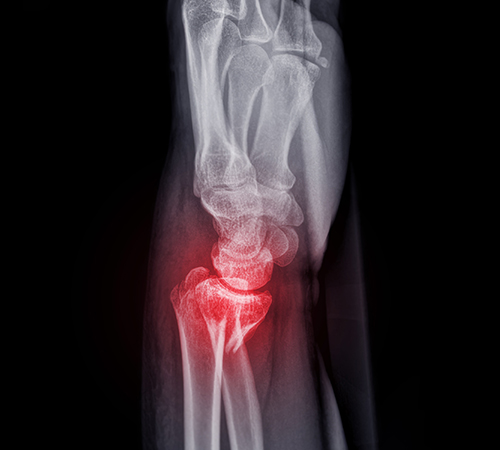

삼각섬유연골복합체파열

• 삼각섬유연골복합체파열

• 삼각섬유연골복합체파열 진단

이학적 검사를 통해 환자의 통증과 증상을 살피고 삼각섬유연골

파열이 의심될 경우 MRI검사를 통해 정밀검사를 진행합니다.

삼각섬유연골파열은 X-ray촬영만으로는 잘 보이지 않기 때문에,

MRI 촬영으로 파열된 모습을 정확하게 확인해야 합니다.